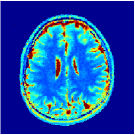

According to [44] as we progress into deeper layers, partitions will be subdivided into smaller segments in a hierarchal fashion. This can be observed in Figure 2 where we adopted the above routine for the T1/T2 encoding MRF sequence used in our experiments and visualised multi-scale (from coarse-to-fine) partitions obtained after each residual layer. The Bloch response manifold is sampled across fine-gridded T1/T2 values (i.e. MRF dictionary) to visualise the intersection of the input space segments with this manifold (results are visualised across the three dominant principal component axes). MRFResnet encoder learns about a thousand partitions for its end-to-end mapping . In the light of (16) we know that for each partition the network implicitly encodes deep matched-filters (the rows of or alternatively ) and an offset term to locally linearly regress the T1/T2 outputs in that segment. As such instead of memorising 100K dictionary atoms used for training, the network learns a compact piece-wise affine approximation to the Bloch manifold projection (5) as a rapid and memory-efficient alternative to DM’s point-wise approximation (7). The total number of parameters used by the MRFResnet (Table I) are two hundreds times less than the size of the dimension-reduced MRF dictionary. Figure 3 shows the Bloch responses for a range of T1/T2 values, as well as deep matched-filters learned by MRFResnet to predict each of these quantities in this range from noisy inputs. Computed through (17), match-filters are one-dimensional analogues of the saliency maps a.k.a. deep dream images [49], measuring sensitivities of the T1/T2 output neurons with respect to the inputs.

Two sets of experiments were conducted here: first, we used the 2D and 3D acquisition sequences for scanning a healthy volunteer’s brain (real-world acquisitions). Figures 6 and 7 display the parametric maps reconstructed from 2D spiral and radial readouts. We computed the T1, T2 and proton density (PD) maps using baseline reconstruction algorithms ZF, VS, LR, FLOR, AIR-MRF and our proposed LRTV. While baselines use DM either for quantitative inference or also during reconstruction (i.e. AIR-MRF), we further compare the DM-free LRTV’s performance when cascaded to DM, KM and MRFResnet for quantitative inference. For the 3D spiral acquisitions we compared LRTV and its closest competitor VS in Figure 8. Outcomes from other tested algorithm are displayed in the supplementary materials (Figure S5). Since FLOR does not use dimensionality-reduction, our system ran out of memory during 3D reconstruction; hence results are not reported in this case.

VI-E1 Discussion

The LRTV-DM and LRTV-MRFResnet perform on par, and both outperform all tested baselines for reconstructing T1, T2 and PD maps in all acquisition schemes. This can be observed both visually in Figures 6, 7, 8, S2 and S3, and quantitatively in Table IV across all tested metrics. Other baselines were unable to successfully remove the under-sampling artefacts in TSMIs, and these errors propagated to the parameter inference phase and resulted in inaccurate maps. Temporal-only priors incorporated within LR are shown insufficient to regularise the inverse problem and LR sometimes (e.g. 2D spiral acquisitions) can admit solutions with even stronger artefacts than the model-free ZF baseline. This issue was previously studied for other non-Cartesian MRF readouts that similar to our spiral/radial trajectories, miss to sample the corners of the k-space in all timeframes (see section 2.2.2 and figure 2 in [19]). In the absence of reference for the k-space corners information, the LR iterations despite minimising the objective can converge to solutions with high-frequency artefacts, as visible in the computed maps. This highlights the need for adding an appropriate spatial-domain regularisation. FLOR reduces the LR’s artefacts but this improvement is limited because the suggested nuclear norm penalty does not incorporate an explicit spatial regularisation. Further for reducing artefacts, FLOR can introduce an undesirable bias in the computed T1/T2 maps e.g. see error maps in Figures S2 and S3. The non model-based VS baseline incorporates spatial regularisation and results in spatially smoother maps than ZF and LR, but it is unable to output artefact-free images. Further and consistent with our in-vitro experiment, we observe that VS overestimates the T2 values (e.g. in White and Grey matter regions) in tested 2D acquisitions i.e. the spatial regularisation trades off agains the quantification accuracy. The model-based AIR-MRF adds spatial regularisation through 2D/3D low-pass Gaussian filters however this trades off the sharpness of the computed maps and can increase the errors at the tissue boundaries (we searched Gaussian spreads that keep the blurs and high-frequency artefacts minimal). For our acquisition readouts, Gaussian filters performed better than disk filters of [19] for avoiding strong Gibbs artefacts. On the other hand, the spatiotemporally regularised LRTV greatly improves the TSMI reconstructions i.e. 4 dB enhancement compared to the closest competitor baseline (Table IV). This enables computing accurate and aliased-free multi-parametric inference using DM or the DM-free learning-based alternative MRFResnet as visible in Figures 6, 7, 8, S2 and S3. MRResnet and DM score competitive quantitative inference results i.e. T1 and T2 MAPE less than 5% and 9%, respectively (Table IV). KM also outputs comparably accurate T1 maps, however this shallow learning model despite having a model size larger than MRFResnet, is unable to learn accurate T2/PD quantification and it results in poor estimated maps, consistent with our observations in section VI-C.